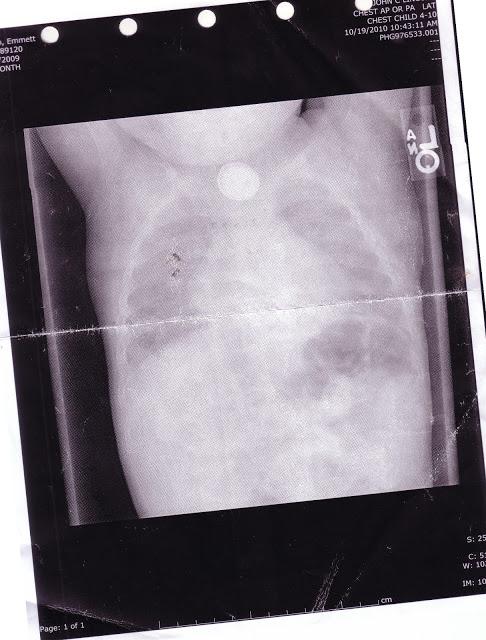

Echipa de doctori i-au făcut o radiografie, au identificat bateria pe film și au înțeles că acidul din mica baterie distruge esofagul și tractul gastro-intestinal al micuțului.